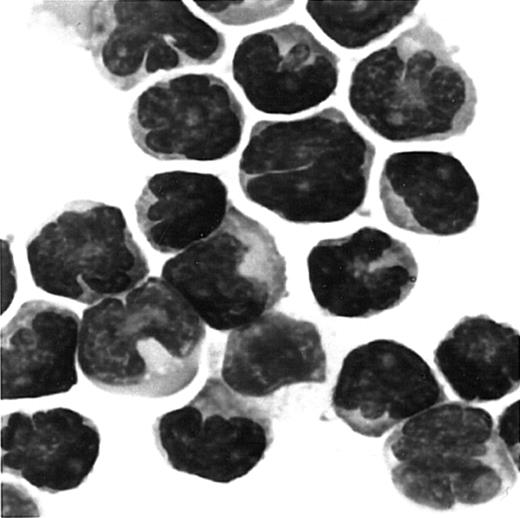

Since ATL cells have characteristic flowerlike nuclei, it is rather easy to identify ATL cells in blood smears. We therefore further carried out immunologic staining of CCR4 using routine blood smears from a total of 7 patients with ATL. Representative results are shown in Figure 4. Again, most ATL cases (6/7) were clearly stained positive for CCR4 (A, B, C: positive; D: negative).

Immunocytologic staining of CCR4 in blood smears.

Routine blood smears obtained from 4 patients with ATL (A-D) were stained for CCR4 as described in “Materials and methods.” Leukemic cells are positive (A, B, C) or negative (D) for CCR4. No staining was seen by an isotype-matched control mouse IgG (not shown).The slides were counterstained by hematoxylin and the original magnification was × 1000.

Giemsa staining of cells migrated to MDC/CCL22.

PBMCs were obtained from a patient with ATL. Cells migrated to MDC in chemotaxis chambers were collected and stained with Giemsa as described in “Materials and methods.” Original magnification, × 1000.